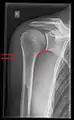

Imaging of the shoulder includes ultrasound, X-ray and MRI, and is guided by the suspected diagnosis and presenting symptoms.

Conventional x-rays and ultrasonography are the primary tools used to confirm a diagnosis of injuries sustained to the rotator cuff. For extended clinical questions, imaging through Magnetic Resonance with or without intraarticular contrast agent is indicated.

Hodler et al. recommend starting scanning with conventional x-rays taken from at least two planes, since this method gives a wide first impression and even has the chance of exposing any frequent shoulder pathologies, i.e., decompensated rotator cuff tears, tendinitis calcarea, dislocations, fractures, usures, and/or osteophytes. Furthermore, x-rays are required for the planning of an optimal CT or MR image.[23]

X-ray

Projectional radiography views of the shoulder include:

- AP-projection 40° posterior oblique after Grashey

The body has to be rotated about 30 to 45 degrees towards the shoulder to be imaged, and the standing or sitting patient lets the arm hang. This method reveals the joint gap and the vertical alignment towards the socket.[24]

- Transaxillary projection

The arm should be abducted 80 to 100 degrees. This method reveals:[24]

- The horizontal alignment of the humerus head in respect to the socket and the lateral clavicle in respect to the acromion

- Lesions of the anterior and posterior socket border, or of the tuberculum minus

- The eventual non-closure of the acromial apophysis

- The coraco-humeral interval

- Y-projection

The lateral contour of the shoulder should be positioned in front of the film in a way that the longitudinal axis of the scapula continues parallel to the path of the rays. This method reveals:[24]

- The horizontal centralization of the humerus head and socket

- The osseous margins of the coraco-acromial arch and hence the supraspinatus outlet canal

- The shape of the acromion

This projection has a low tolerance for errors and, accordingly, needs proper execution.[24] The Y-projection can be traced back to Wijnblath’s 1933 published cavitas-en-face projection.[25]

CR. shoulay film.